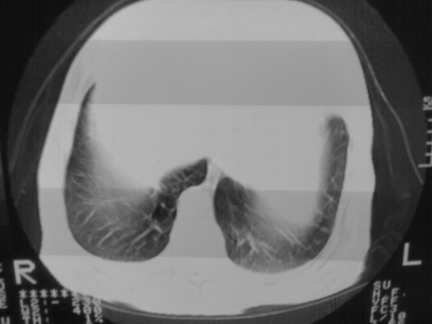

标题: CT13142:女 80 胸闷、气短、1w [打印本页]

标题: CT13142:女 80 胸闷、气短、1w

右肺炎性变

双侧胸腔积液

胸膜肥厚,

气管,支气管软骨钙化。

右肺感染;双侧胸腔少量积液,心影增大,可能与心功不全有关;胸内甲状腺肿。

胸内甲状腺肿;右肺感染;双侧胸腔少量积液。

胸内甲状腺肿;右肺中叶感染;双侧胸腔少量积液;心影增大,考虑有心功能不全。